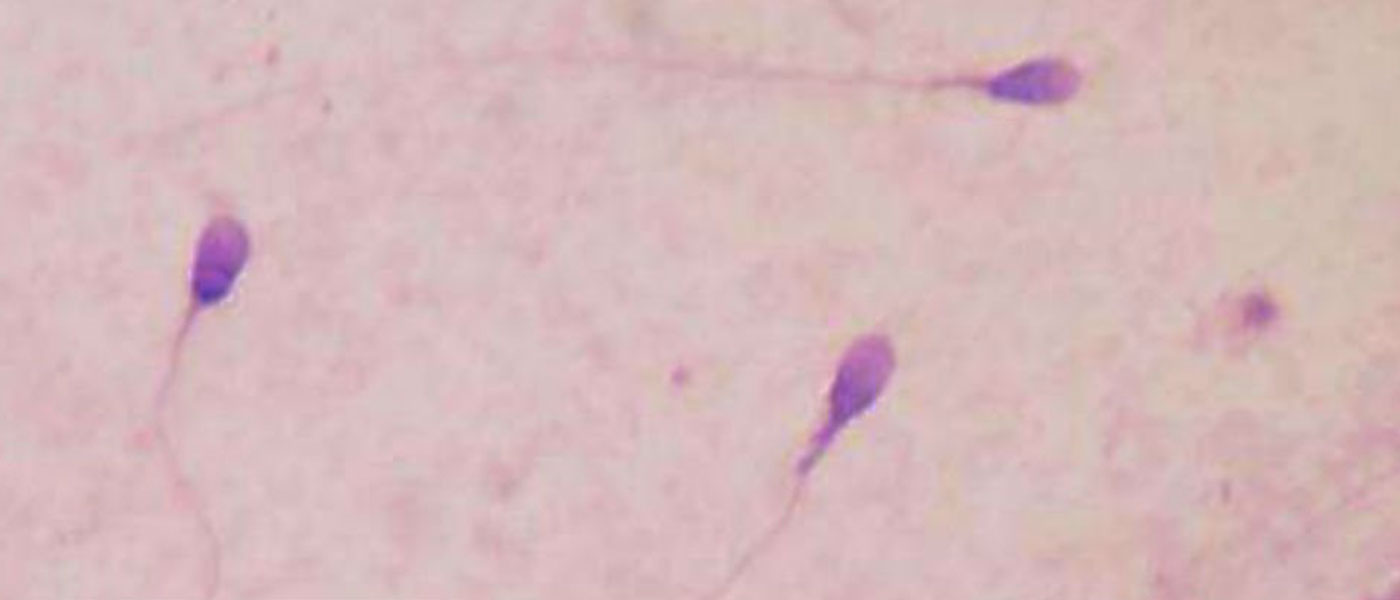

Couples who rely on donated sperm or eggs to conceive may soon have a new option. Scientists in Spain have managed to turn human skin cells into germ cells, which can eventually be developed into sperm or eggs using a ‘gene reset’ procedure.

To accomplish this, the team added a “cocktail of genes” to skin cells, which turned into germ cells after about a month. While the germ cells could be developed into sperm, they wouldn’t have the ability to fertilize, because a further mutation phase is required to create a gamete, says Simon.